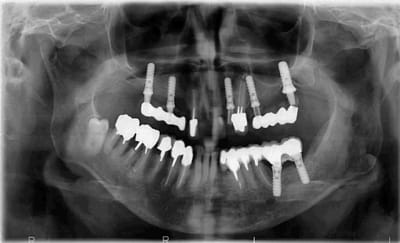

intéressants, les implants zygomatiques qui s'arrêtent au quart du chemin. d'un point de vue biomécanique, ce traitement implantaire, c'est n'importe quoi. les édentements terminaux à droite et à gauche doivent être soutenus par 3 implants minimum, de préférence ostéo-intégrés, et de préférence pas dans la cavité sinusienne (il se peut que les implants soient placés dans une paroi sinusienne en évitant la cavité, mais je doute). la ligne de gencive sur l'implant en 22 est irrécupérable, car il n'y a rien pour soutenir une greffe. ce que je ferai:

1-examen scanner pour voire exactement ou se baladent ces implants.

2-dépose des implants douteux, je pense par exemple à l'implant distal à gauche.

pour moi, c'est condamné non seulement en haut à gauche mais aussi en bas à gauche...

en haut à droite, il y a trop peu d'implants et le bras de levier par rapport à l'axe implantaire est trop important...

cette bouche est en train de s'effondrer.

secundo: tu ne peux arriver à t'en sortir au maxillaire pour une longue durée à moins de virer toutes les dents et de procéder à une greffe et ROG en haut à hauche après avoir déposé l'implant 27, et donc tu dois PLANIFIER les extractions dentaires, le placement des racines artificielles, la dépose de l'implant 27, la surélévation sinusale,plus la greffe d'apposition certainement nécessaire et la ROG associée...

tertio: quand l'infection anaérobique est maîtrisée, démonter les provisoires, effectuer un prélèvement ramique en bas à gauche (à conserver en liquide physiologique), lambeau bien disséqué (pour la fermeture) de 17 à 27 et LA TOTALE EN UNE SEANCE...avec extractions dentaires, pose des implants 15, 13, 12, 11, 21, 23, 25, vissage des vis de couverture (y compris celles des implants déjà posés), dépose de l'implant 27, sinus lift, greffe d'apposition, chips d'os tout autour et au-dessus des implants, membranes par dessus tout le bazar, fermeture hermétique, et la soupe pour un mois.